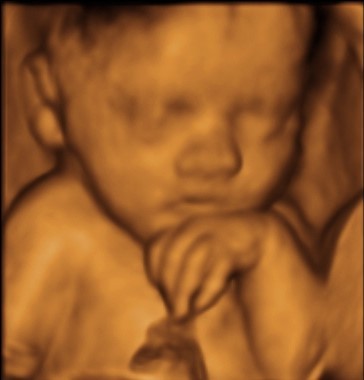

So…what the hell is 4D? Your usual NHS scan will be 2D; enough to see the position of the baby, identify gender after 20 weeks and determine any potential anomalies. In a nutshell 3D scans show far more detail of your baby, including facial features, and 4D scans show moving 3D images, with time being the fourth dimension. 3D scans produce photographs; 4D scans produce video footage.

By this stage of pregnancy the baby has filled out nicely, whilst still allowing plenty room for manoeuvre in the womb. It’s also possible to pick out family features at this stage, and even see how much hair they have!

“There’s a huge TV screen to watch the baby moving around in real time, and Mo explained things in detail as we went along, answering lots of questions. The whole experience was really informative, and gave us a little glimpse into our baby’s world. I couldn’t believe how detailed the picture was- we saw everything from nostrils to the lens of our baby’s eye!” (Please note the images used here are for illustration, they are not from Aine's scan).